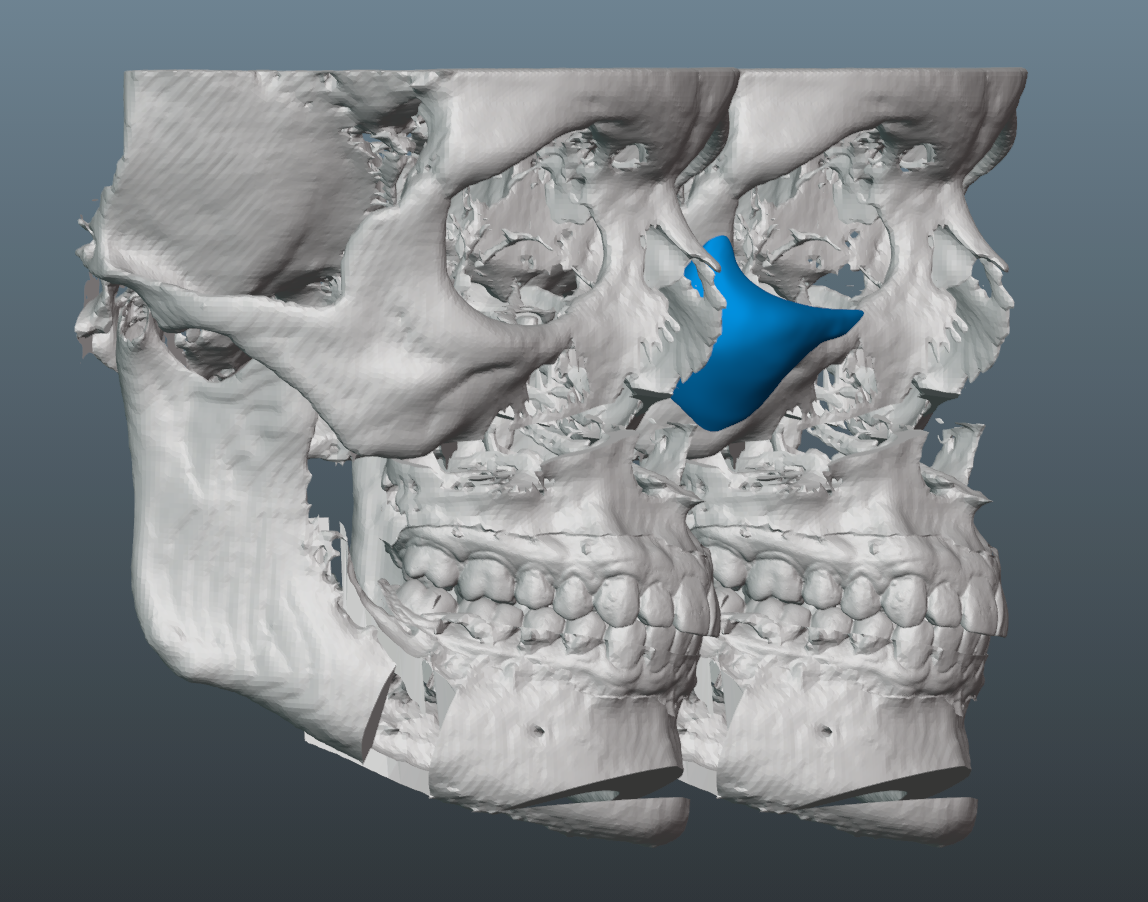

Trimax with around 7mm forward movement and 4mm downgraft.

10.5mm pogonion increase.

Needed a lot of projection on the malar part of the implant, since the patient has a fairly flat midface, which would have been exacerbated by the bimax.

Few key notes and thoughts on the implant design:

-6mm malar projection.

-3mm saddle on the infras.

-Minimal projection on medial part of infra region. This helped keep the taper minimal and avoids too much of the infamous infra implant shelfing/step-off.

-Though we initially tried to do a smaller implant, it became clear that it was necessary to increase its size, so that we could ensure better transitions to the submalar region, zygo arch and lateral orbital rim.